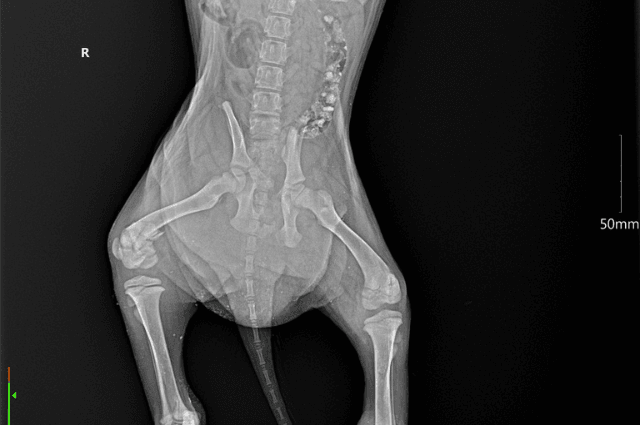

Ten pohled plný bolesti a bezmoci nejde nezapomenou. Jedno štěně prosilo očima, druhé se schoulilo, jako by chtělo zmizet ze světa, který mu tolik ublížil. Operace byly náročné a teď jim titanové šrouby a destičky drží nožičky pohromadě.